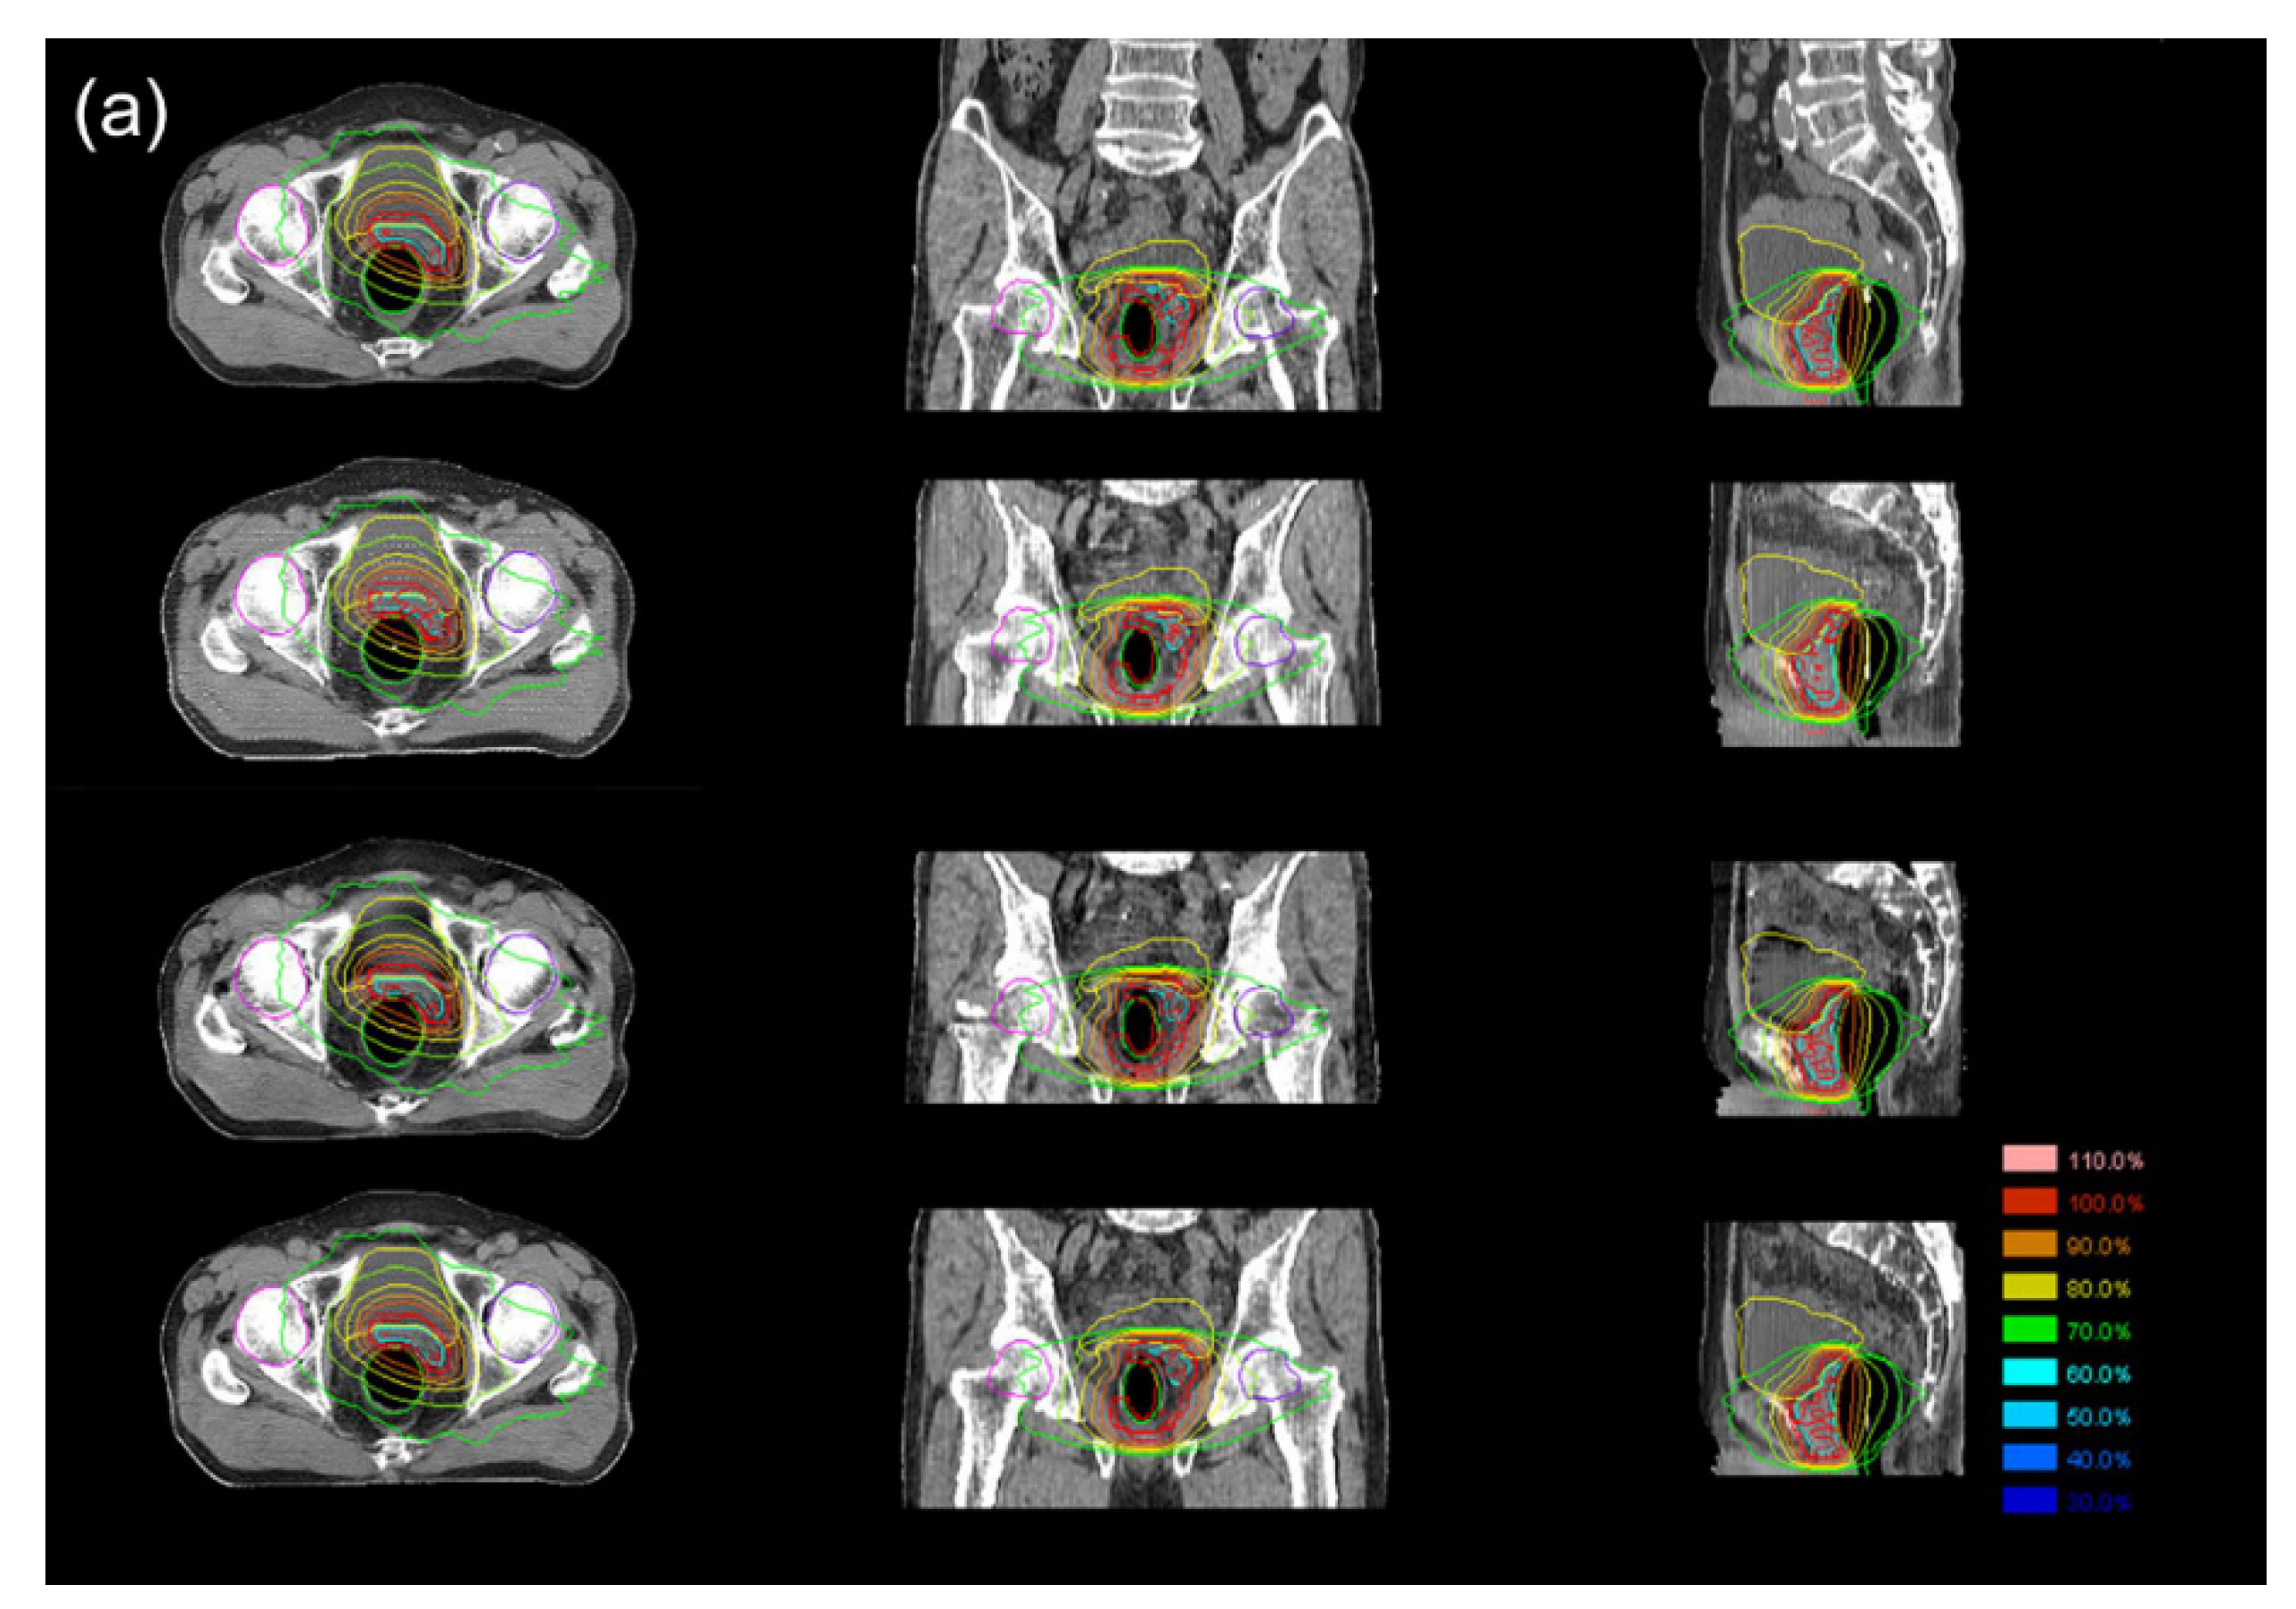

3.3. Dosimetric Comparison